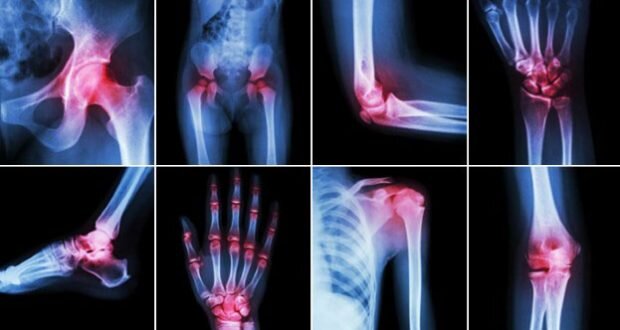

Различные причины появления суставных болей Почему болят суставы и что делать в этих случаях, будет гораздо легче понять, если знать о причинах, вызывающих ломоту, рези в конечностях и ограничение их двигательных функций. Вот ряд самых распространенных суставных болезней:

1. Ревматоидный артрит. Хроническое заболевание, при котором наблюдаются воспалительные процессы в соединительных тканях. Характерные симптомы, сопровождающие артрит:

Болевые ощущения в одном или нескольких суставах нарастают постепенно, в течении одной-двух недель либо могут возникнуть внезапно.

В состоянии покоя боль усиливается, особенно это проявляется в утренние часы.

Ревматоидным артритом могут поражаться как крупные суставы рук и ног (лучезапястные, голеностопные, локтевые, коленные), так и мелкие сочленения стоп и кистей.

Воспаление одного сустава называется моноартритом, нескольких - полиартритом.

Один из симптомов рассматриваемого заболевания - ограничение подвижности больных конечностей в течение первых часов после утреннего пробуждения.

Болезнь сопровождается заметным увеличением суставов, покраснением кожи в проблемном месте и повышением ее чувствительности.

2. Ревматизм. При этом хроническом заболевании постепенно поражаются все органы (сердце, почки, лимфатическая система и т. д.), в том числе и суставы. Процесс может длиться долгие годы. Очень важно начать лечение как можно раньше. Один из наиболее характерных признаков начинающегося ревматизма - это как раз суставные боли, возникающие периодически, иногда сопровождающиеся повышенной температурой тела и отеками.